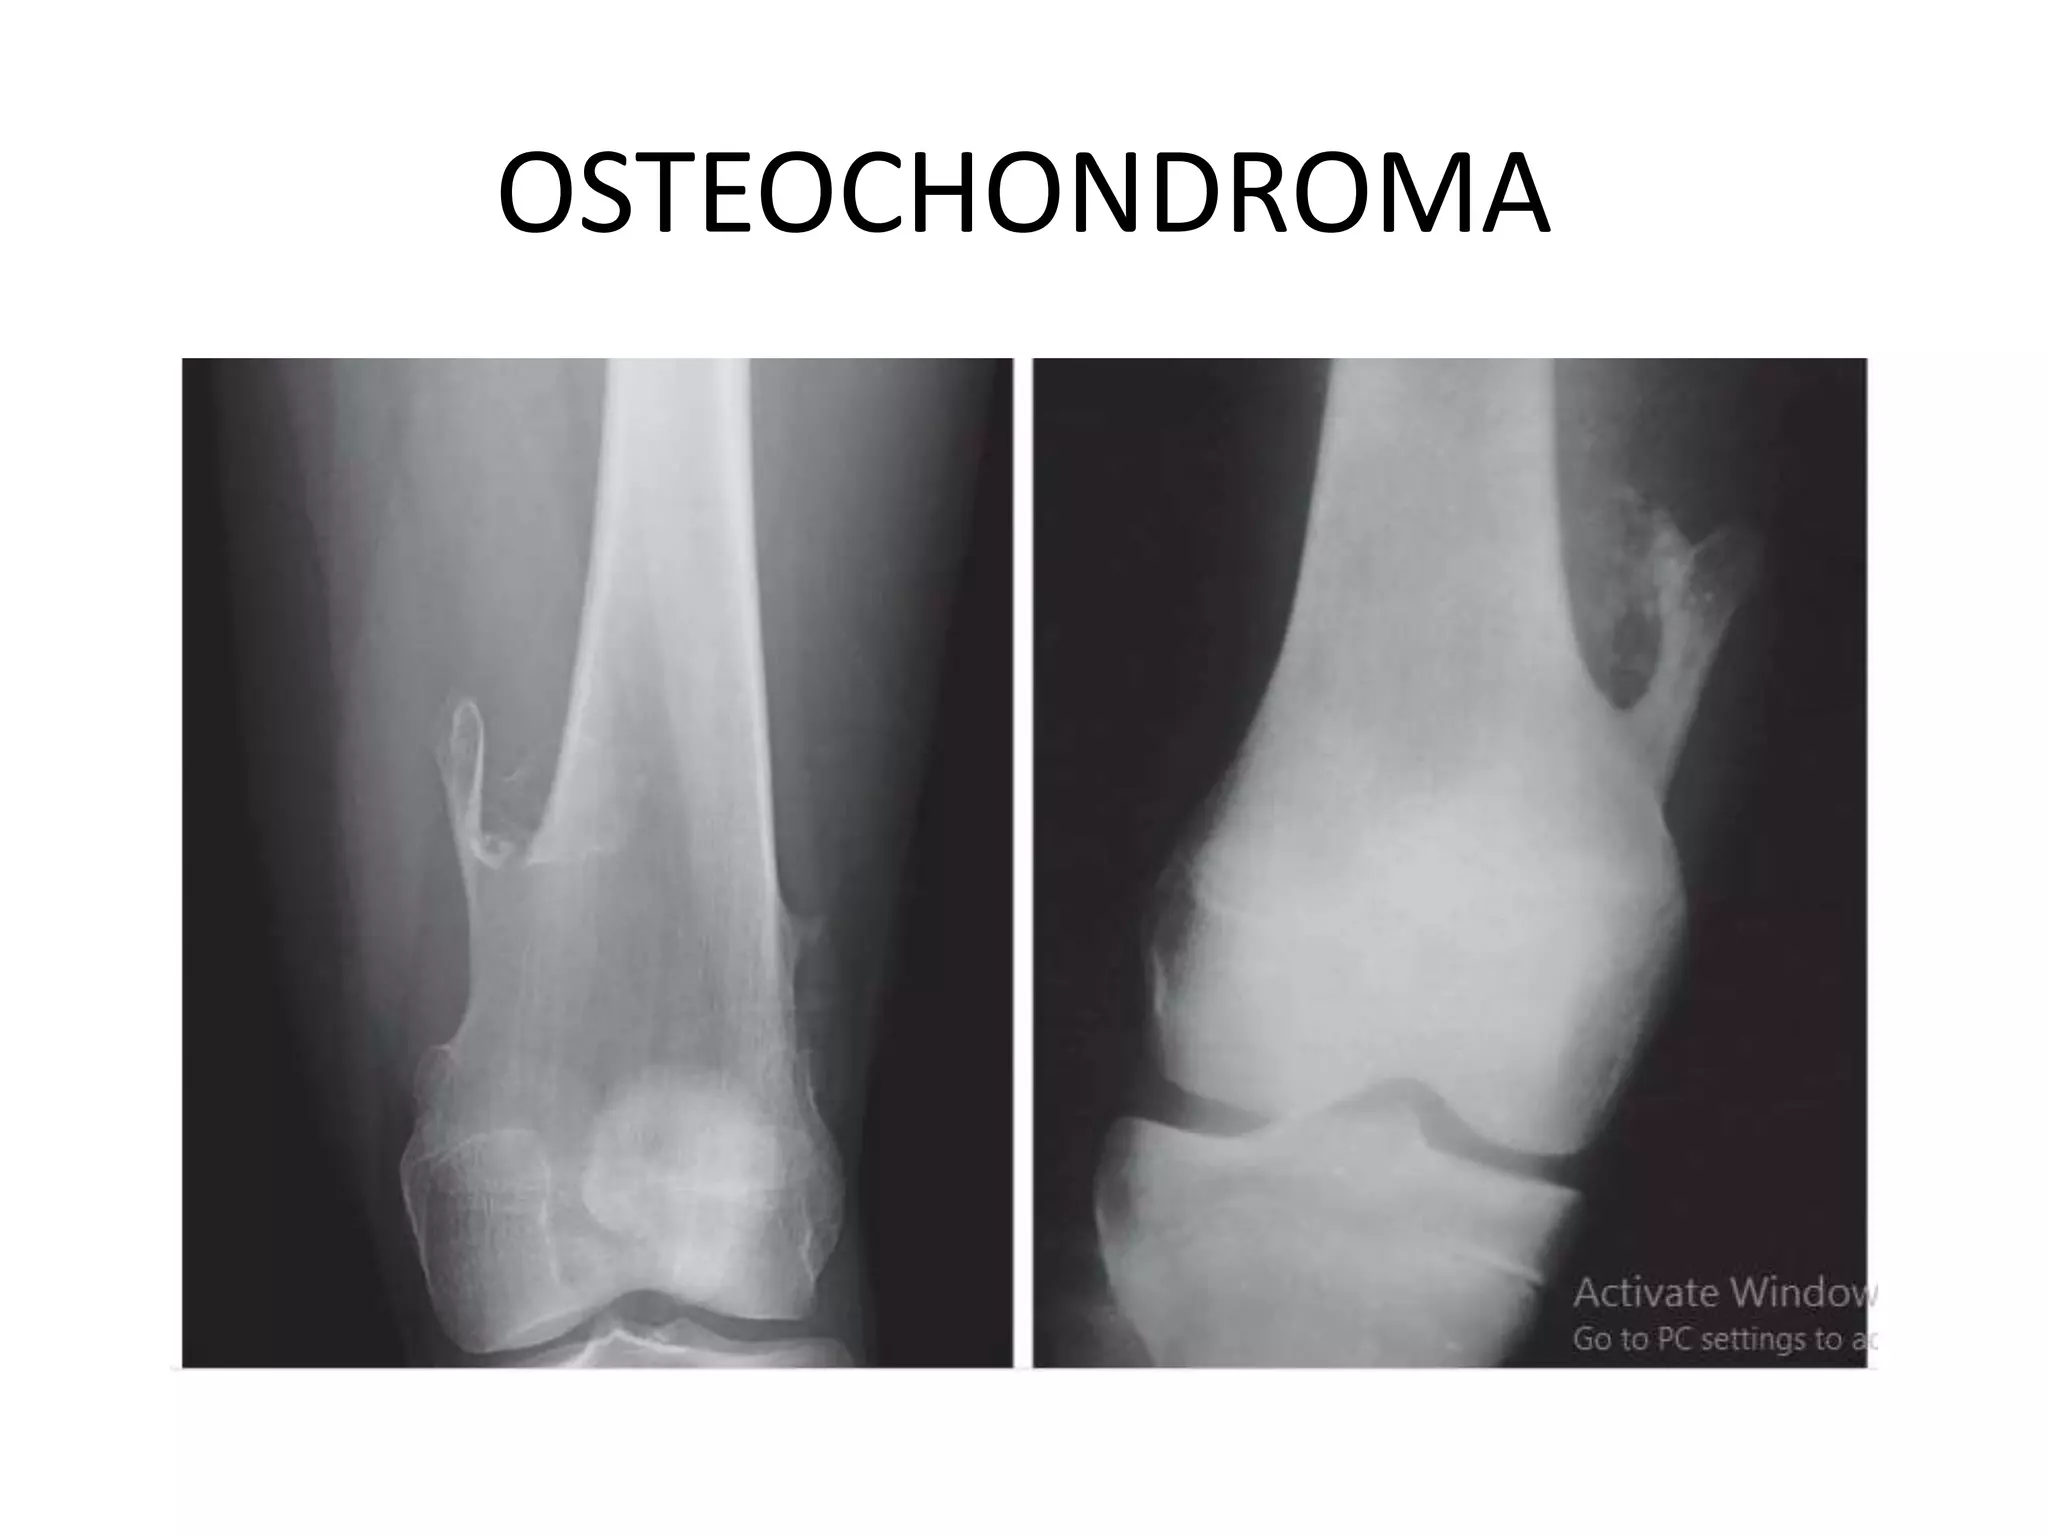

OSTEOCHONDROMA

• Common benign bone tumors

• The lesions consist of a bony mass, often in the

form of a stalk, produced by progressive

endochondral ossification of a growing

cartilaginous cap.

• Common sites- distal femur, the proximal tibia,

and proximal humerus

• Osteochondromas are of two types: pedunculated

and broad based or sessile.